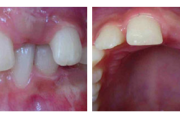

Esimese jäävmolaari ektoopiline lõikumine

Ravijärgne seis. Jäävhammas on täielikult lõikunud.

) Röntgenülesvõte. Ülemise esimese jäävmolaari lõikumine on takistatud 2. piimamolaari tõttu